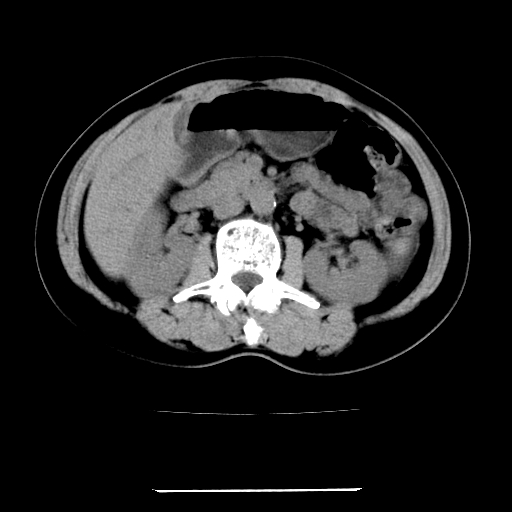

女,67岁,上腹部疼痛一周伴皮肤黄染,无发热。

1、肝门高密度影下层面和胰头层面可见轻度胆管扩张,而静脉和延迟期均未见扫描完胰头,不能完全排除胰头占位。2、肝门部高密度影,考虑钙化或结石。

考虑肝胆管癌;胰头占位?【形态失常,体积增大】

考虑肝门胆管癌伴门脉左支受侵包埋,建议mrcp进一步检查。